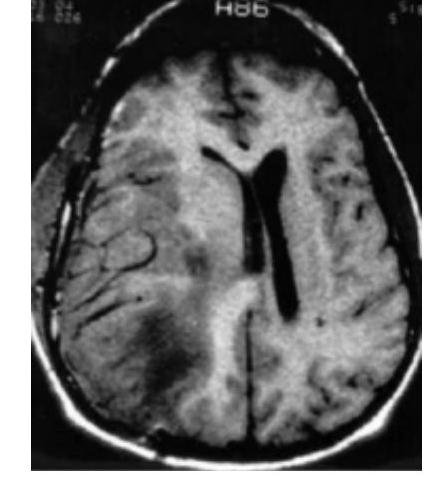

# SÍNDROMES DE HERNIACIÓN Efecto de **masa expansiva intracraneal** que ocupa espacio 1. Hernia del **cíngulo** 2. Hernia transtentorial **central** (diencefálica) 3. Hernia transtentorial **lateral** (uncal) 4. Hernia **cerebelosa** (Amigdalar) ## PATRONES DE RESPIRACIÓN EN COMA **RESPIRACIÓN DE CHEYNE-STOKES** - PACIENTE EN **DECORTIACIÓN**  Hernia Amigdalina  # HERNIA UNCAL - Uncus del lóbulo temporal - **MIDRIASIS UNILATERAL** - (compresión nervio ocular común) - Hemiparesia contralateral  Signo clave - PUPILA **IPSILATERAL** FIJA Y **DILATADA** ## HERNIA SUBFALCINA - Parénquima por debajo de la **hoz** - Comprime la arteria cerebral **anterior** - Es **preámbulo** de la hernia **transtentorial**  ## HERNIA TRANSTENTORIAL O CENTRAL - **Hemisferios cerebrales** hacia abajo - **MIOSIS** - **Babinski** - Respiración **Cheyne-Stokes** (apneas **de 10-30 s**, aumento progresivo de amplitud hasta llegar a apnea de nuevo)  # HERNIA CEREBELOSA AMIGDALAR O INFRATENTORIAL - Hernia de la **amígdala** a través del foramen oval - **MUERTE**